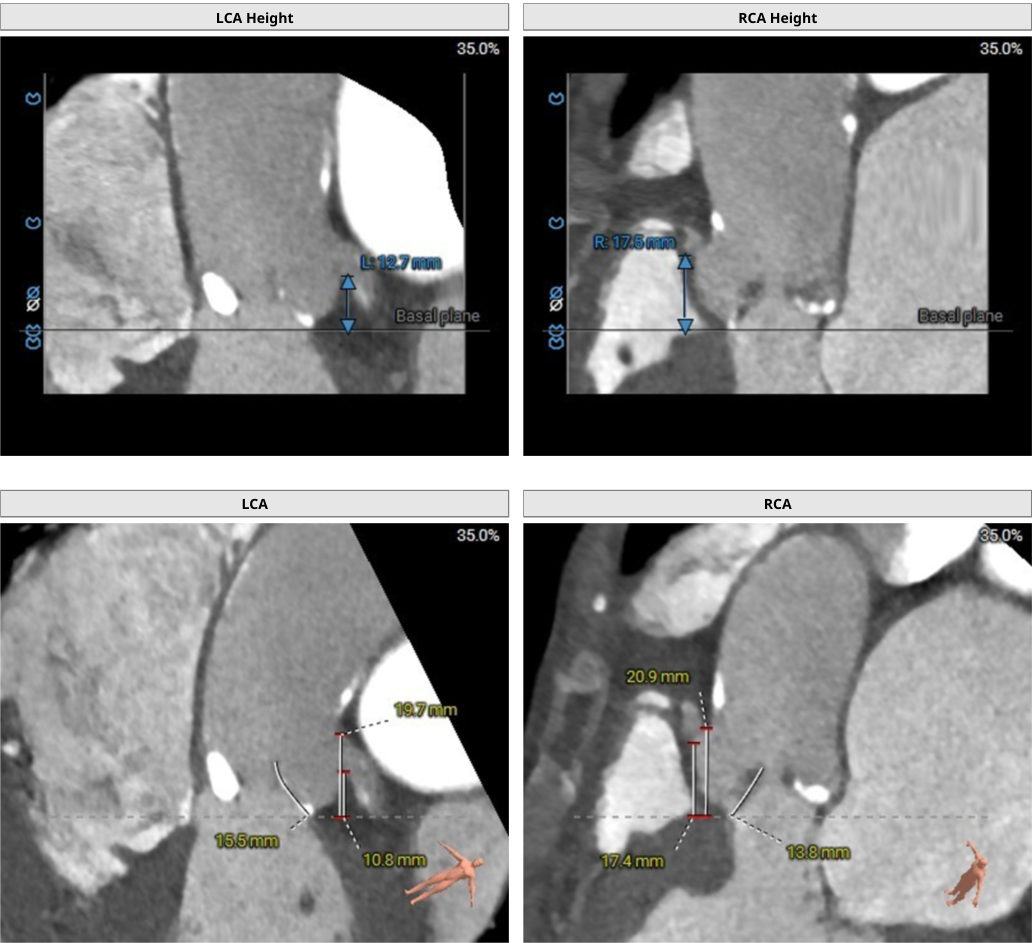

术前CT评估

三叶瓣,右无交界钙化融合。850HU阈值下测得总钙化599mm³。钙化主要分布于右无及左无交界,瓣叶缘及窦底,其中右无交界 钙化经无冠窦瓣叶缘及窦底,延伸至LVOT下约8.0mm。瓣环面积433.1mm²,LVOT面积393.7mm²,SOV30.9-34.7mm,STJ高度25.6mm,内径28.6-32.9mm。右冠细小,考虑左冠优势型,MPR视图下测得左冠开口高度10.8mm,左冠开口上缘19.7mm,左冠瓣叶长度15.5mm;右冠开 口高度17.4mm,右冠开口上缘20.9mm,右冠瓣叶长度13.8mm。模拟23#Renatus,左冠VTC6.5mm,右冠VTC7.1mm。左冠开口较低,瓣叶冗长,且右无交界钙化较重。

使用Supra annulus画圆法评估23#RENATUS瓣膜植入情况: